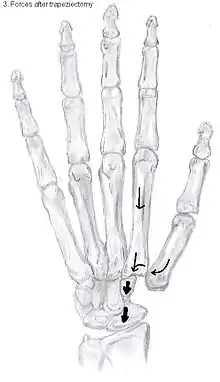

Showing the forces after trapeziectomy

In one randomized trial comparing trapeziectomy alone with trapeziectomy with ligament reconstruction and trapeziectomy with ligament reconstruction and tendon interposition, patients evaluated 5 to 18 years after surgery had similar pain intensity, grip strength and key and tip pinch strengths after each procedure.[29] Trapeziectomy alone is associated with fewer complications than the other procedures.